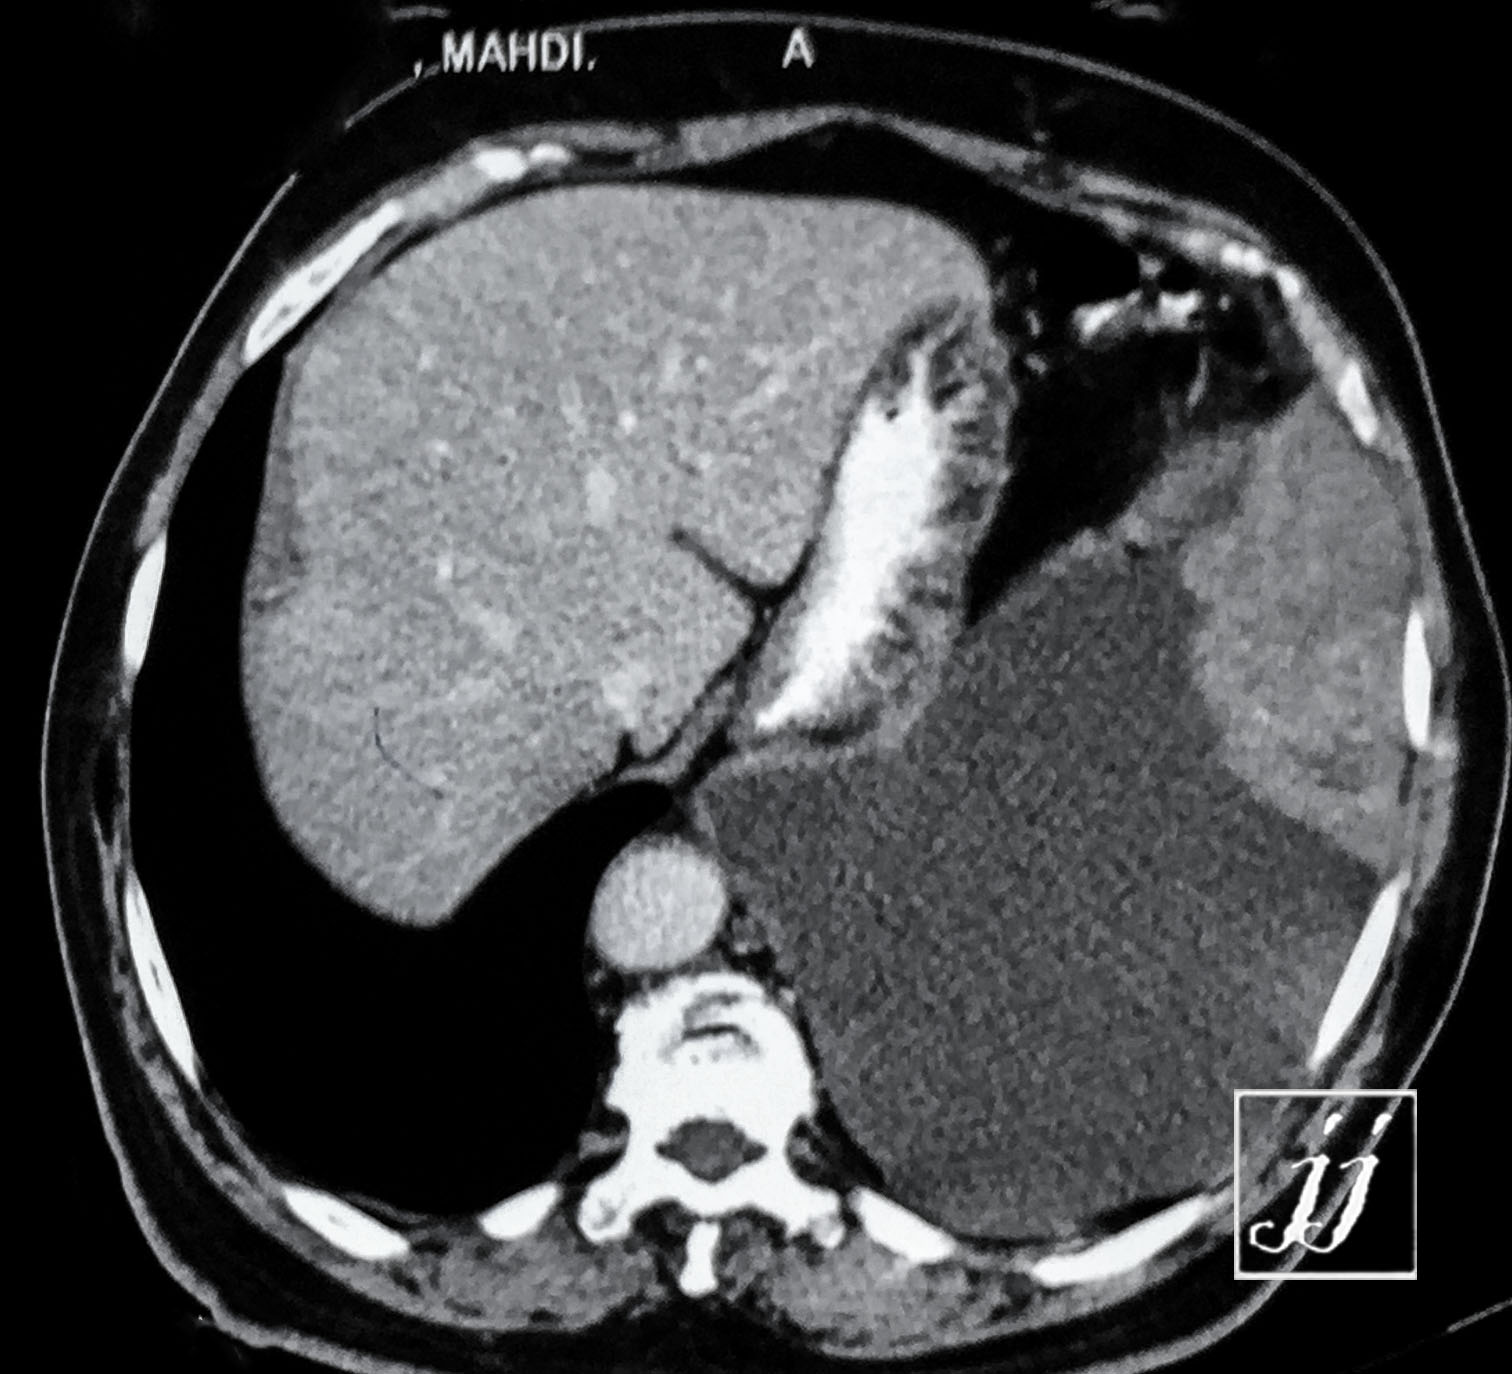

Abdomen- left side plural effusion (6)